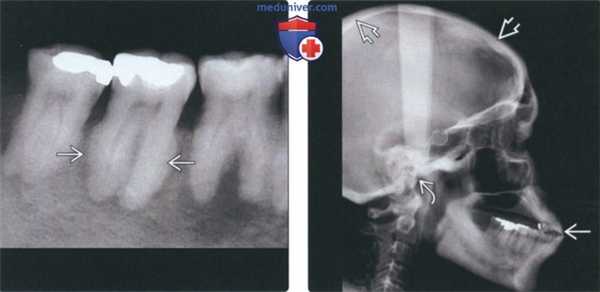

(Слева) На периапикальной рентгенограмме у этого же пациента определяется гиперцементоз корней второго моляра нижней челюсти справа с изменением твердой пластинки в соответствии с педжетоидной картиной поражения костной ткани. Пространства периодонтальной связки сужены или отсутствуют.

(Справа) На рентгенограмме черепа в боковой проекции у этого же пациента определяется утолщение губчатой кости и склероз основания черепа. Увеличение челюсти приводит к выступанию резцов кпереди и мальокклюзии. Верхняя челюсть в этом случае не поражена.